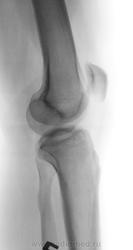

Пол пациента: Мужской пол Тип патологии: Травма Область исследования: Скелетно-мышечная система Методы исследования: Rg Травма, 50 лет, падение на колено, хирург искал перелом надколенника. Что за очаги оссификации? https://radiomed.ru/sites/default/files/styles/case_slider_image/public/user/17212/3.jpg?itok=ZOARUHOu https://radiomed.ru/sites/default/files/styles/case_slider_image/public/user/17212/4.2.jpg?itok=FzC0cneJ https://radiomed.ru/sites/default/files/styles/case_slider_image/public/user/17212/4.jpg?itok=jE1z60Rz ID:28343 Thu, 02/05/2013 - 13:17 #1 И.Бондаренко Offline Last seen: 13 hours 12 min ago Joined: 13.09.2011 - 22:55 Posts: 9206 Возможно обычная остеопойкилия. Thu, 02/05/2013 - 22:30 #2 Almo Offline Last seen: 18 hours 5 min ago Joined: 28.09.2008 - 18:50 Posts: 8259 +1.

Возможно обычная остеопойкилия.